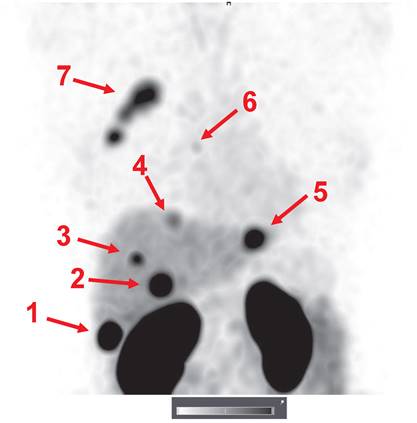

An important observation was that the hepatic metastases were clearly visualized in patient 15 (Figure 7). Hepatic metastases occur frequently in HER2-positive breast cancer [50], and their visualization is a precondition for successful clinical translation for a HER2-specific imaging agent. Interestingly, the uptake level in several liver metastases far exceeded the uptake in the primary tumor. Most likely, this can be explained by the high blood perfusion of the liver.

Figure 7

Visualization of hepatic metastases 2 h after injection of 1000 µg 99mTc-ZHER2:41071. The uptake values (SUVs) for the hepatic metastases (arrows) were 1-75.7; 2-44.4; 3-22.1; 4-14.6; and 5-35.2. A metastasis in a parasternal lymph node (6) was also visualized (SUV max = 6.9). The uptake in the primary multicentric tumor (7) was 22.3. Linear SUV scale from 0 to 20.